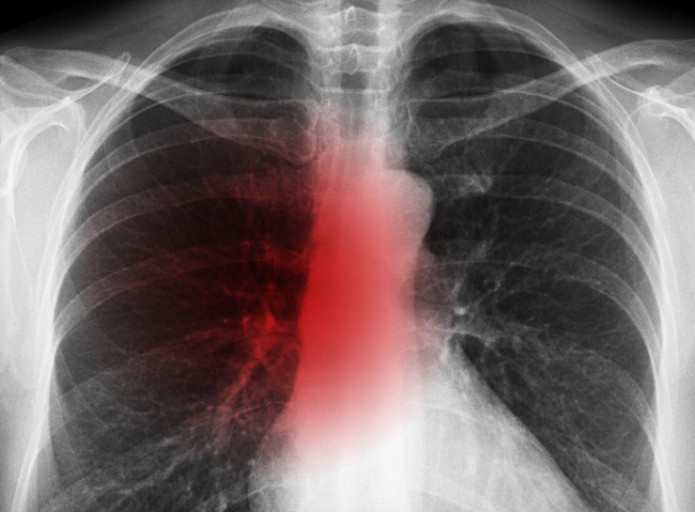

3. 숨 쉴 때 쌕쌕 거리는 소리가 난다.

보통 숨소리는 크게 들리지 않지만, 목이나 폐 부분에 뭐가 걸린 느낌이 나듯이 숨소리가 거칠어지는 걸 느낍니다.면 폐에 문제가 생겼을 확률이 높다. 꼭 내원해 엑스레이를 촬영해 보는 게 바람직합니다..